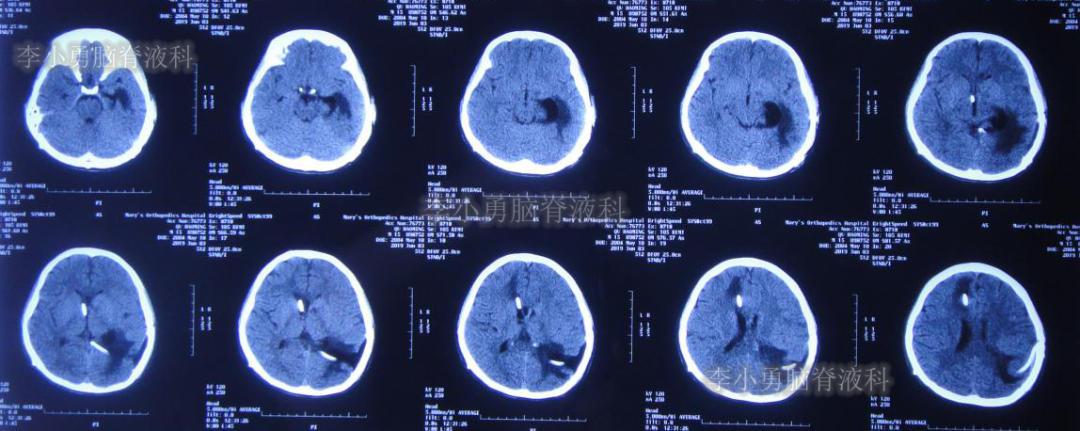

左侧颞角引流术后33天即2019年8月1日,给予试夹闭右侧脑室外引流管,闭管前复查头颅CT(图-22)。

图-22:2019年8月1日夹闭前复查头颅CT

闭管40天后即2019年9月9日复查头颅CT(图-23):脑室仍无扩大。给予拔除右侧脑室外引流管并行左侧颞角-腹腔分流术。

图-23:2019年9月9日头颅CT:拔除右侧脑室外引流管后复查

出院后2个月即2019年12月9日,复查头颅CT示脑室系统较出院时无明显变化(图-25);但患者记忆力仍差。

图-25:2019年12月9日头颅CT

出院后9个月即2020年7月6日,再次复查头颅CT(图-26):未见异常。家属叙述:肢体活动正常,记忆力较前有些改善但较同龄人仍差,已重返校园(图-27)。

图-26:2020年7月6日头颅CT:未见异常